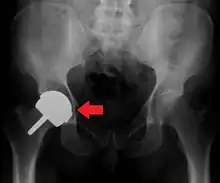

Hemiarthroplasty

Hemiarthroplasty is a surgical procedure that replaces one half of the joint with an artificial surface and leaves the other part unchanged. This class of procedure is most commonly performed on the hip after an intracapsular fracture of the femur neck (hip fracture). The procedure is performed by removing the head of the femur and replacing it with a metal or composite prosthesis. The most commonly used prosthesis designs are the Austin Moore and Thompson prostheses. A composite of metal and high-density polyethylene that forms two interphases (bipolar prosthesis) can be used. The monopolar prosthesis has not been shown to offer any advantage over bipolar designs. The procedure is recommended only for elderly/frail patients, due to their lower life expectancy and activity level. This is because over time the prosthesis tends to loosen or to erode the acetabulum.[100] Independently mobile older adults with hip fractures may benefit from a total hip replacement instead of hemiarthroplasty.[101]

X-ray of the hips, with a right-sided hemiarthroplasty